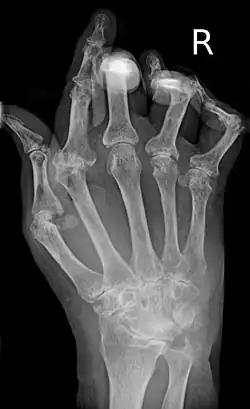

A hand severely affected by rheumatoid arthritis. This degree of swelling and deformation does not typically occur with current treatment.

As the pathology progresses, the inflammatory activity leads to tendon tethering and erosion and destruction of the joint surface, which impairs range of movement and leads to deformity. The fingers may develop almost any deformity depending on which joints are most involved. Specific deformities, which also occur in osteoarthritis, include ulnar deviation, boutonniere deformity (also "buttonhole deformity", flexion of proximal interphalangeal joint and extension of distal interphalangeal joint of the hand), swan neck deformity (hyperextension at proximal interphalangeal joint and flexion at distal interphalangeal joint) and "Z-thumb." "Z-thumb" or "Z-deformity" consists of hyperextension of the interphalangeal joint, fixed flexion, and subluxation of the metacarpophalangeal joint and gives a "Z" appearance to the thumb.[16]: 1098  The hammer toe deformity may be seen. In the worst case, joints are known as arthritis mutilans due to the mutilating nature of the deformities.[20]